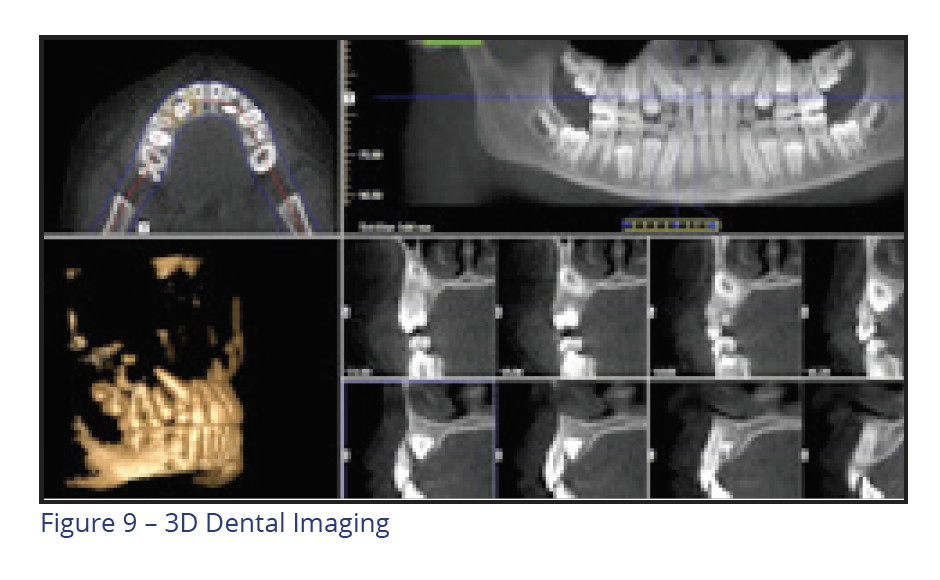

Orthodontic Records

Cone beam 3D dental imaging is becoming more popular to gather information needed to evaluate and diagnose a case. 3D views are used to analyze teeth, roots, TMJ, airway, and sinuses without magnification or distortion. Practice efficiency can be enhanced by capturing a complete workup in less than 10 seconds. This is especially helpful when the practitioner intends to place TADs or when knowing the exact position of teeth is important to determine the best treatment plan. A virtual study model can be utilized to prevent the need for taking study model impressions (Figure 9).